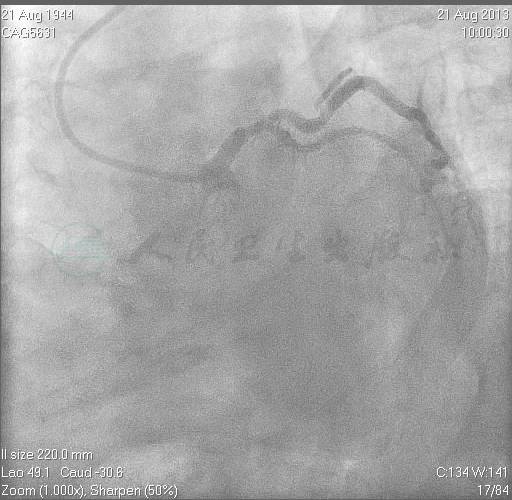

近期外院造影结果提示:左主干、回旋支、中间支血管大致正常;前降支开口完全闭塞;右冠脉中段支架良好,可见侧支供应前降支血管(图1~图4)。

图3 右冠脉中段支架无明显内膜增生,提供侧支至前降支

图4 右冠脉造影,右侧位,提供前降支侧支